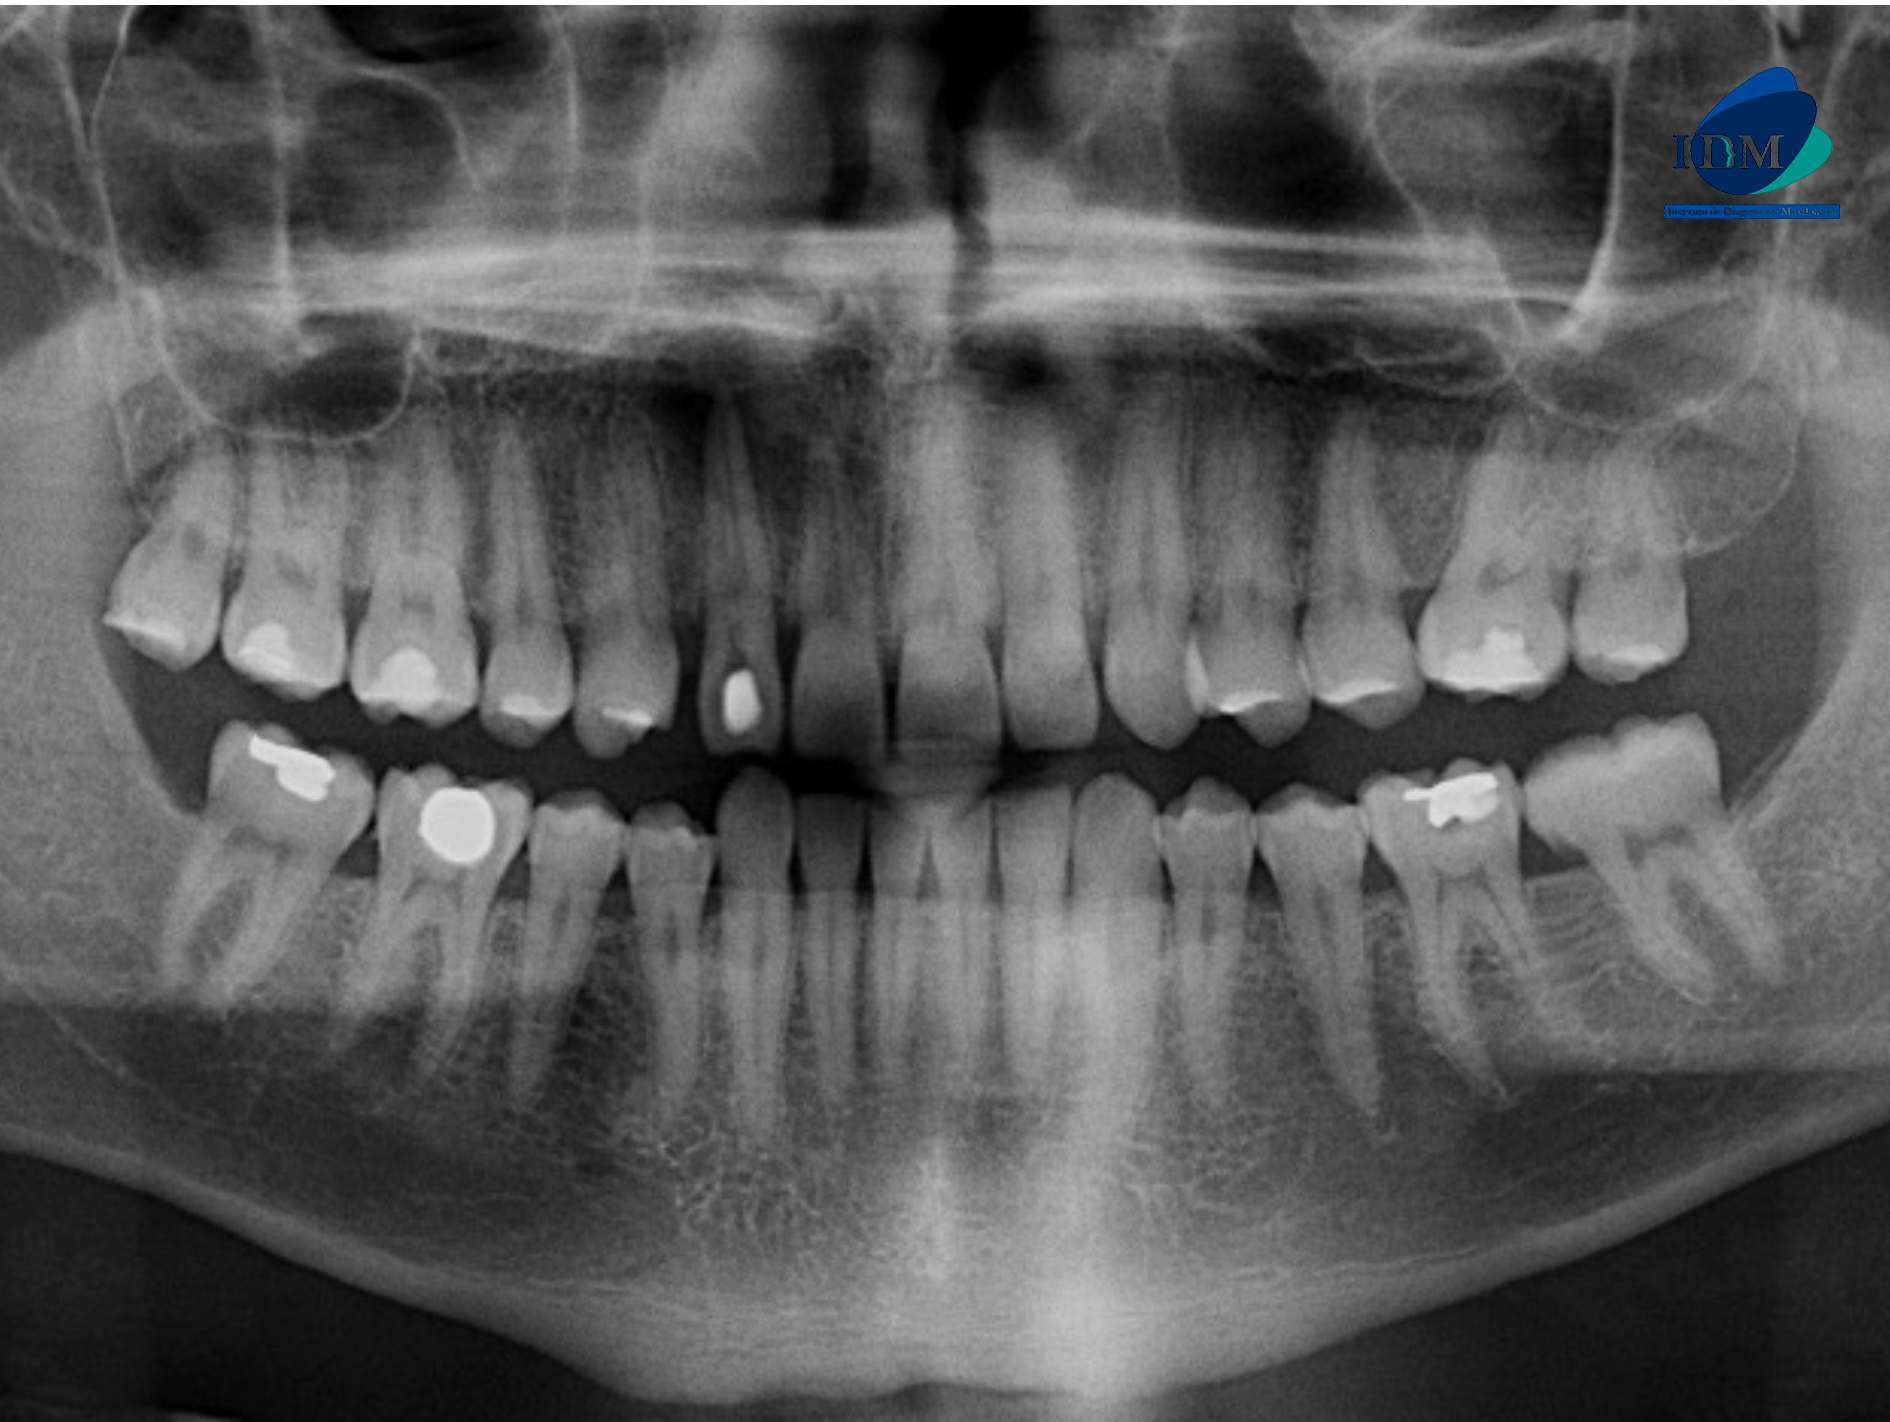

Paciente masculino de 37 años de edad acude al Instituto de Diagnóstico Maxilofacial con el motivo de consulta: descartar fractura radicular.

Radiografia Panorámica

A la evaluación de la radiografía panorámica se observa la neumatización de ambos senos maxilares, la presencia de placa cervical mineralizada, atrición de piezas dentarias anteriores y múltiples restauraciones coronarias. La pieza 22 presenta material restaurador en cara libre y un trazo radiolúcido de forma vertical paralelo al conducto pulpar, así también se observa un proceso osteolítico periapical parcialmente corticalizado.